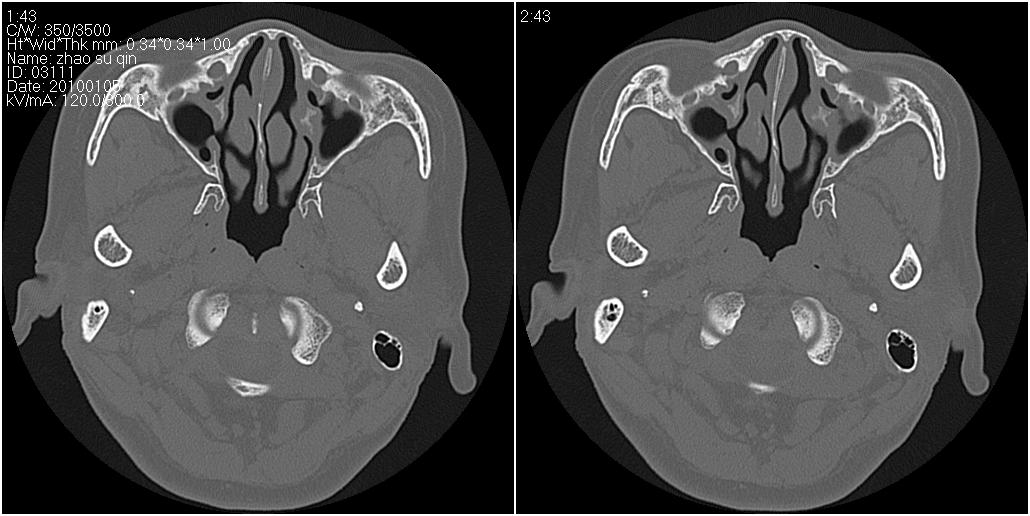

标题: CT24015:一个头部外伤患者进行鉴定,除了左侧筛板骨折,哪 [打印本页]

标题: CT24015:一个头部外伤患者进行鉴定,除了左侧筛板骨折,哪

看了几遍,其余未见明显骨折征。

左眶下裂部好像有骨折 似有小碎骨片

1)左侧筛板骨折。2)双侧筛窦炎症(或积血)。

其余未见明显骨折征。